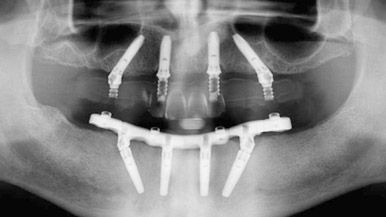

The 3 on 6 Treatment begins with a Comprehensive Evaluation. A 3D CBCT Scan and Panoramic X-Ray let us know If you have a huge deterioration of bone, decreasing bone density, or reduction of height/width of bone, this information helps us to determine if you are a candidate for this treatment.

Planning Implants Placement

As a result of a Comprehensive Evaluation, our Specialists make the best plan for dental implants placement taking into count the quality of your bone.

Once an adequate prosthetic plan has been established, the patient will be ready to receive dental implants. Surgical Guides and NAVIDENT (Dynamic Navigation for Dental Implantation) facilitate ideal implants placement.